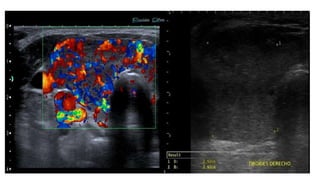

• #49 Heterogeneously enlarged thyroid gland with decreased color Doppler signals. hypoechoic micro nodules